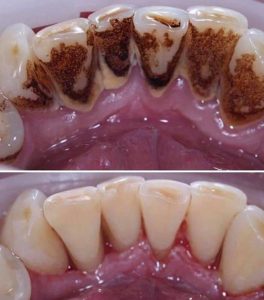

Tratamientos Ortodoncia Blanqueamiento dental Zoom Contacto 72 2795 9597 Marcar Ahora Envia whatsapp Visita nuestro facebook